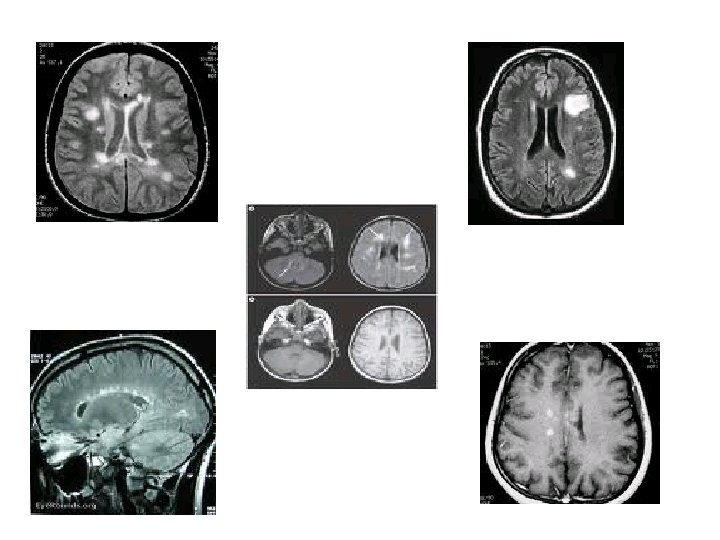

Classification of Changes on Brain Magnetic Resonance Images Graded 0 to 4 based on the following criteria – Number of lesions – Size and shape of lesions: • <3 mm, > 20 mm – Location of lesions: • periventricular, peripheral white matter, grey matter, brainstem, cerebellum and corpus callosum

MRI and risk of developing MS • CIS – Clinically isolated event [ monocular optic neuritis ] • CDMS – Clinically definite MS

Without MRI findings • At 5 years ----- 16% • At 10 years ----- 22% Only 3% increased risk after 10 years • At 15 years ------ 25%

With MRI findings • At 5 years ----- 37% with 1 -2 lesions 51% with ≥ 3 lesions • At 10 years ------ 56% with ≥ 1 lesion 20% increased risk after 10 years • At 15 years ------ 75% with ≥ 1 lesion

ONTT • The results of the ONTT are applicable to monocular demyelinating typical optic neuritis • Beware of applying these results to all cases presenting with “optic neuritis” • In general, the visual outcome is usually good irrespective of treatment • The MRI (T-2 weighted 1. 5 Tesla ) is an extremely important prognosticator future MS